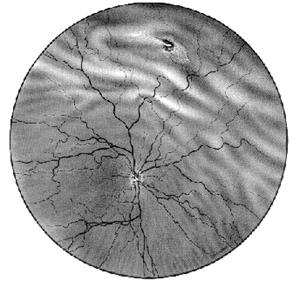

Fig. 17.9 - Decolare de

retina - aspect oftalmoscopic

Examenul oftalmoscopic - se face prin oftalmoscopie directa

si indirecta. Retina decolata are aspect cenusiu si se onduleaza usor la

miscarile ochiului (caracterul mobil). Dupa decubit dorsal mai

multe ore retina se reaplica partial si decolarea este de mai

mici dimensiuni. La nivelul retinei decolate vasele fac cot si au traiect

ondulat. De asemenea la examenul oftalmoscopic este necesara

evidentierea rupturilor retiniene, deoarece tratamentul include

fotocoagularea acestor zone prin care se acumuleaza lichid in spatiul

de clivaj (Fig. 17.9 - vezi

plansa).